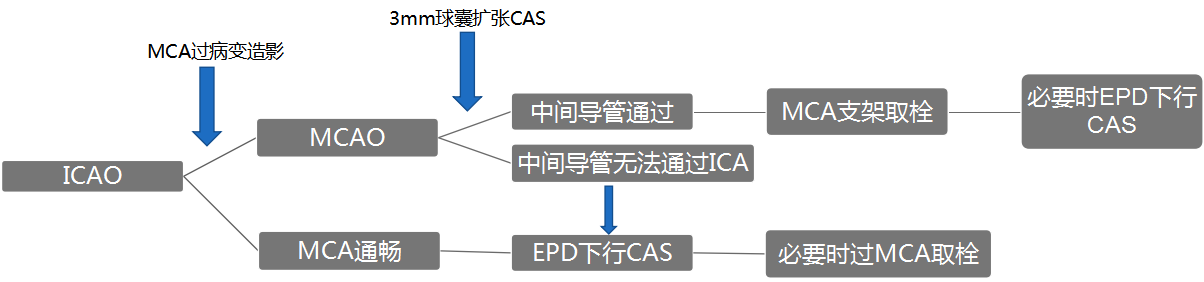

技术细节:

· 串联闭塞如何快速建立颅内的治疗通路

· 如何避免近端颈动脉再次栓塞

· 如何缩短复流所需时间

我中心的流程策略